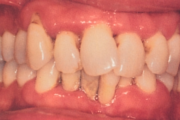

Krooniline parodontiit

Krooniline parodontiit on mikroobide poolt põhjustatud hammaste tugikudede põletik, mille tulemusena tekib progresseeruv alveolaarluu (nähtav röntgenograamil) ja periodontaalligamendi destruktsioon, igemetaskute moodustumine, igeme retsessioon või mõlemad kahjustused kombineeritult. Loe edasi »

- igemed veritsevad (19)

- igemed punetavad (21)

- igemed on tursunud/vohavad (17)

- igemepiir on taandunud (3)